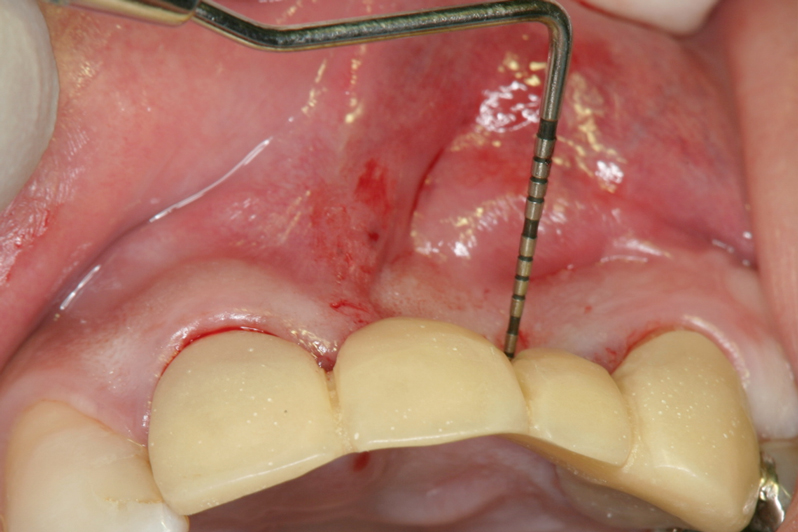

【右上1番SST 口蓋側歯根の抜歯】

【左上2番 SST 口蓋側歯根の抜歯】